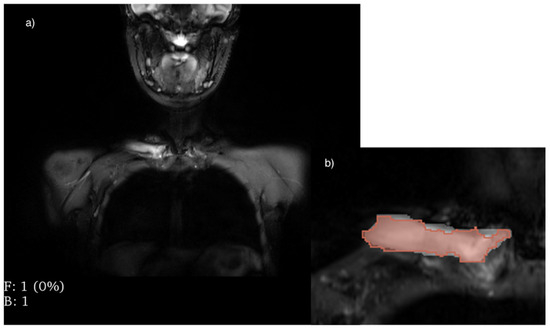

2.3. Processing of Images and Extraction of Features

- von Brandis, E.; Jenssen, H.B.; Avenarius, D.F.M.; Bjørnerud, A.; Flatø, B.; Tomterstad, A.H.; Lilleby, V.; Rosendahl, K.; Sakinis, T.; Zadig, P.K.K.; et al. Automated segmentation of magnetic resonance bone marrow signal: A feasibility study. Pediatr. Radiol. 2022, 52, 1104–1114. [Google Scholar] [CrossRef]